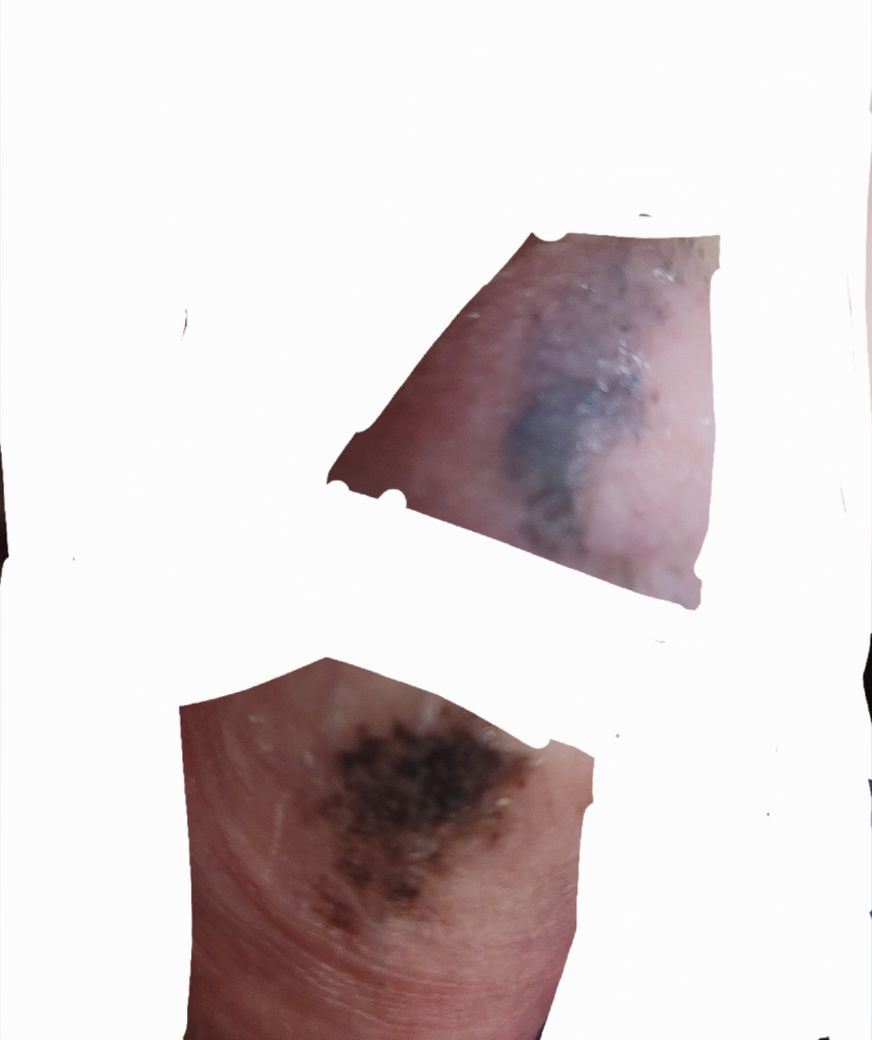

어렸을때부터 성기에 점 비슷하게 있다고 인지하고 있었는데 최근에 보니 점이 더 짙어지고 커진 느낌입니다

위 사진은 2017년 7월에 찍어둔 사진이며

아래 사진은 어제 찍은 사진입니다

통증이나 가려움증은 전혀 없습니다

확실히 이전보다 크기가 증가하고 경계가 불분명해지는 것이 사실이기

때문에 조직 검사를 하는 것이 필요한 것으로 보입니다. 부위가 민감한 부분

이기는 하지만 점차 진행하고 있는 것이 사실이기 때문에 대학 병원 피부과

모양이 일반 반점이라고 하기에는 불규칙하고

흑색종의 특징을 갖고 있습니다.

사진으로 보여주신 병변을 보면 경계가 울퉁불퉁해서 대학병원 진료를 받아보시는게 맞다고 판단됩니다.